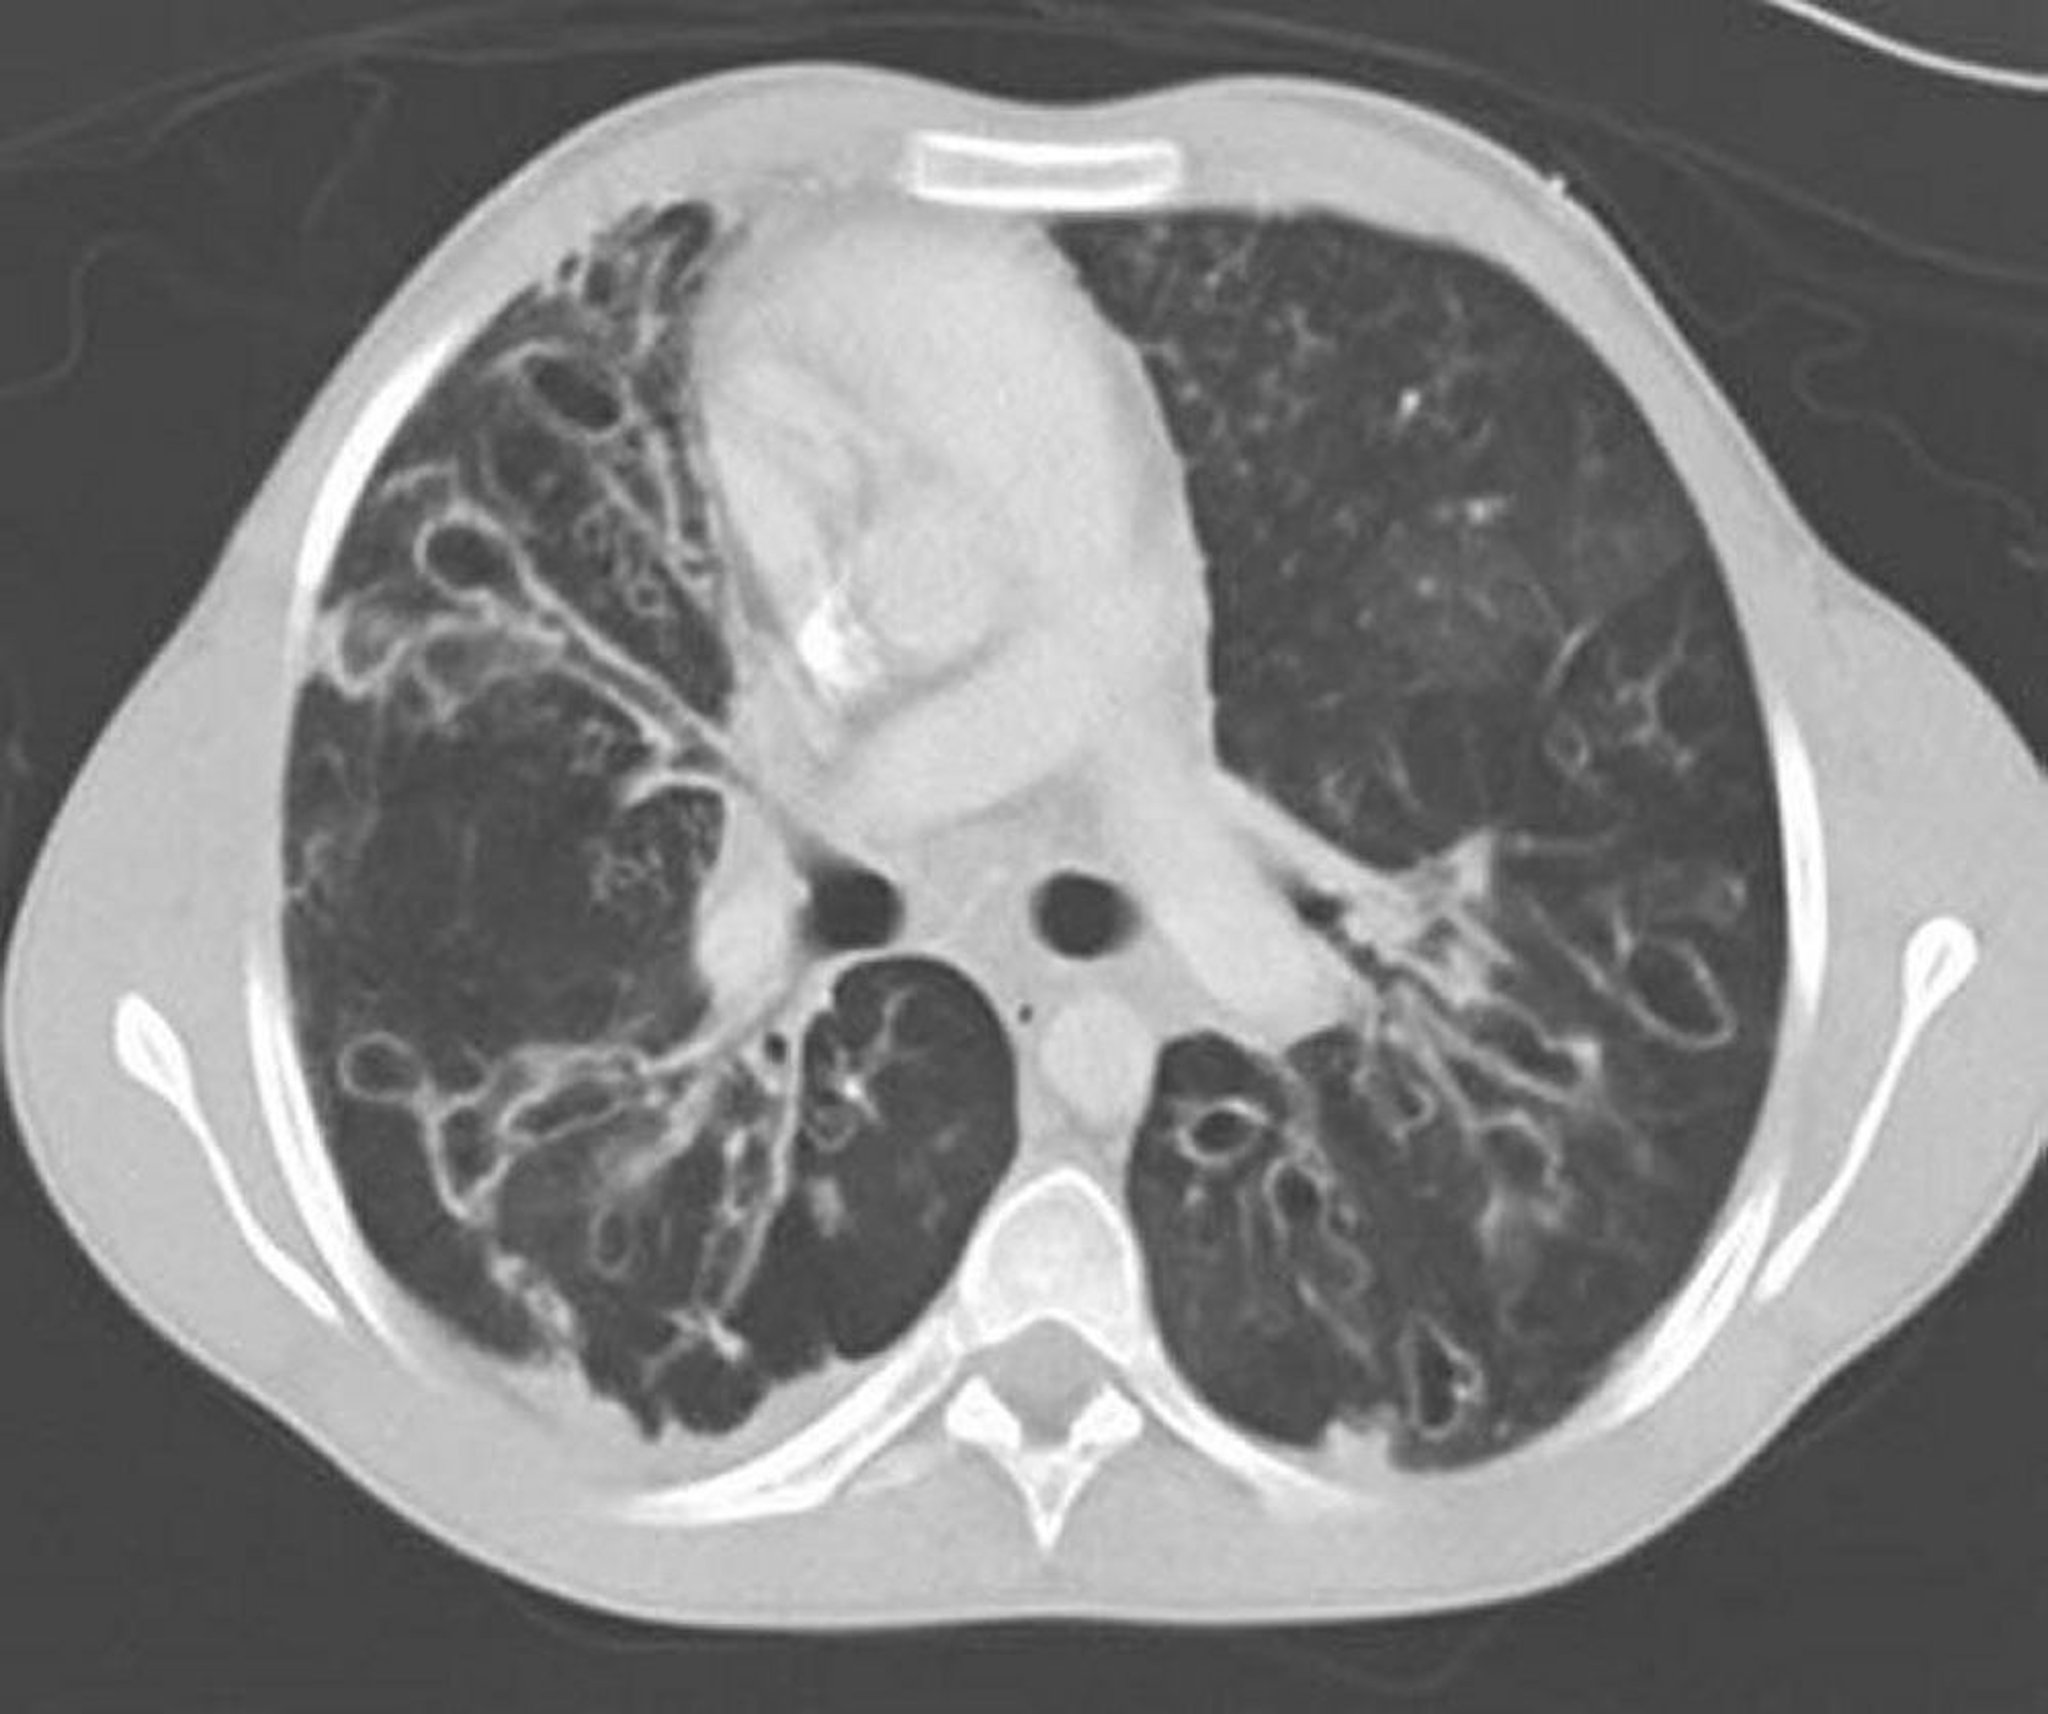

Aspergillose bronchopulmonaire allergique (bronchectasies)

Une TDM thoracique avec contraste montre des bronchectasies sévères dans les zones médianes du poumon avec des voies respiratoires grossièrement dilatées et ectasiques ainsi que des modifications kystiques. L'ectasie des voies respiratoires est caractérisée par un rapport des voies respiratoires au vaisseau adjacent > 1.